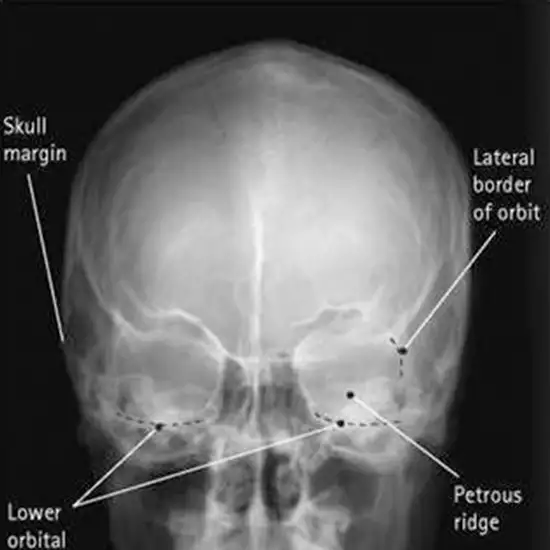

Internal Acoustic Meatus (Internal Auditory Canal) locates in the temporal bone and exists between the inner ear and posterior cranial fossa.

X-Ray Internal Acoustic Meatus Per Orbital is a non-invasive radiology procedure that is used to assess internal acoustic meatus and diagnose the underlying issues.